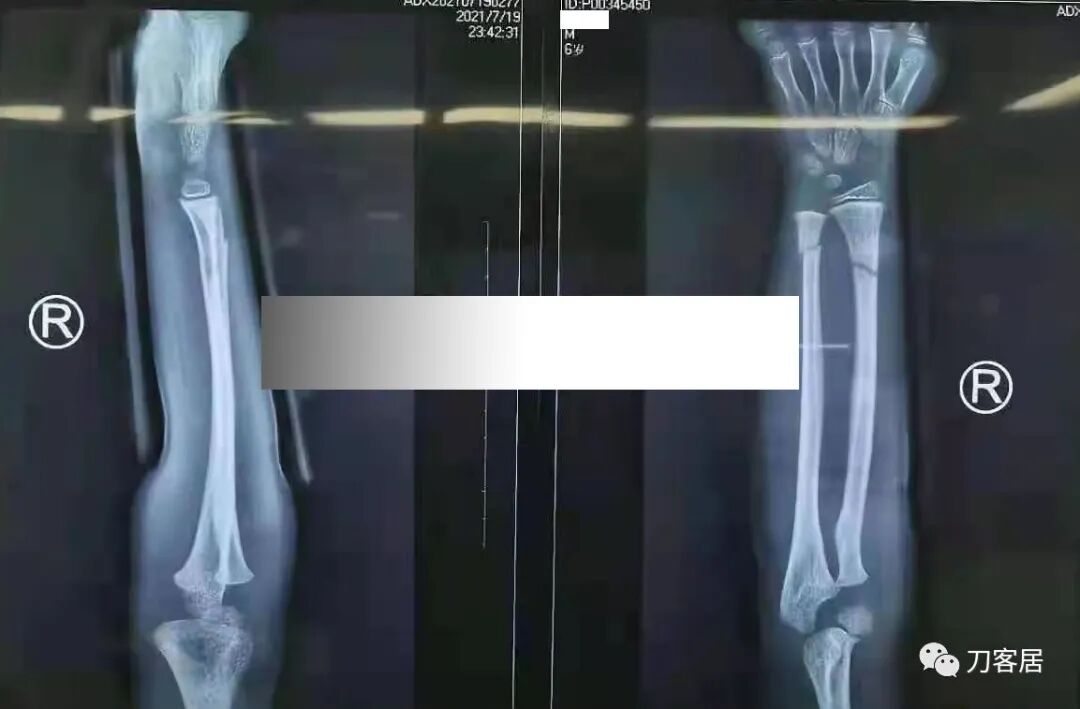

下面是这个6岁孩子,尺桡骨远端双骨折的术前及术后片子和外观照片。

1.  这是一个很简单的6岁儿童无移位的尺桡骨远端骨折。没有皮肤损伤,没有移位,没有骨折碎块儿。

2.  这个骨折处理起来也很简单,单纯的打石膏托或者中医的小夹板,或者正规的包括腕关节和肘关节的管型石膏外固定4周即可治愈该骨折。实在不行,如果这个孩子比较听话,不太调皮的话,用一本书,一个三角巾悬吊固定4周,都可以治愈该骨折。但是给这个患者用外固定架做了手术,而且桡骨远端的几颗克氏针距离骨折线太近,其中一枚克氏针进入到骨折间隙内。从这个术中图片来看,术者的外固定手术技术也有待于进一步的提高。毕竟术者应该还很年轻。从X线片来看,前臂及手的尺侧有不透光影,应该还使用了外固定石膏绷带托,而且我猜测应该是高分子的石膏绷带托,这个是纯属猜测,不一定是对的,不过如何解释前臂尺侧的不透光影呢?如果真是用了石膏绷带外固定的话,那为啥要做手术呢?外固定架术后就不该再用石膏绷带托辅助了。

3.  对于肢体骨折,特别是前臂长骨骨折,双骨折虽然不稳,但更容易手法复位,往往单骨折手法复位比较困难。该病例患儿6岁,尺桡骨双骨折,没有移位,所以根本就不存在需要复位的,直接打石膏外固定即可。孩子年龄越小,塑形能力越强,愈合速度越快,即使是有轻度的畸形骨愈合,在未来的塑形过程中,自然而然的恢复正常的力线和功能。对于该病例,即使是不干预,再过1-2周,只要骨折断端不移位,也能正常愈合而不留任何畸形。